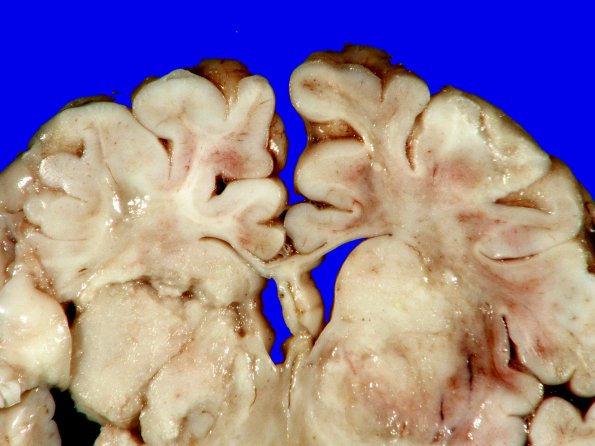

10B5 Hypoxia-Ischemia, neonatal (ulegyria) (Case 10) Gross_7B

Higher magnification of image #10B4.